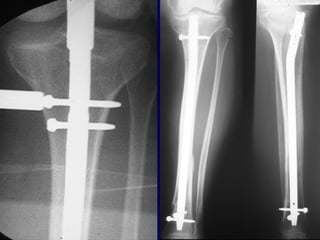

Stability

When

To

Interlock?

Loss of Alignment without

Interlocking Nails

• Spiral 7/22

• Transverse 0/27

• Metaphyseal 7/28

• Templeman CORR 1997